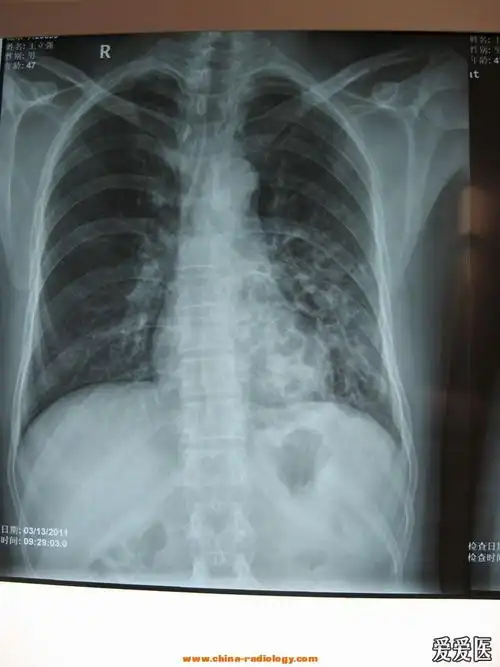

支气管扩张典型图片

胸部,x光,支气管炎,支气管树,胸腔

经典胸片展示之三--支气管扩张